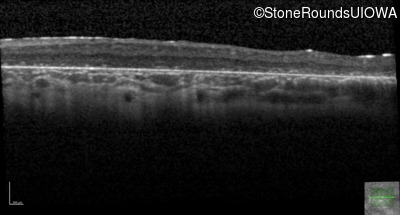

AR Stargardt Disease (IIA)

Age at visit: 6 years

This 6 year old male first experienced a loss of visual acuity at age 5. His acuity was previously normal. He is otherwise healthy.

Diagnosis & molecular findings

Disease Gene Allele 1 variant(s) Allele 2 variant(s) Inheritance mode

AR Stargardt Disease ABCA4 IVS9+1 G>A IVS37+1 G>A AR